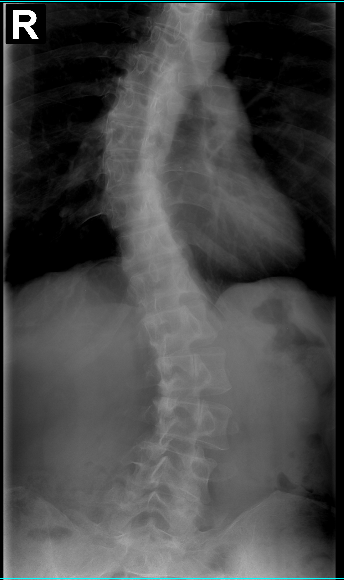

Frequently, the Schroth Method is referred to as a three-dimensional treatment technique. Scoliosis causes the spine to compress, shift, and rotate. It is a pathology that occurs in three planes. This technique, a unique approach, works on the transverse, sagittal, and coronal planes of the body. The exercises achieve the optimum result when all the pathological spinal deformities are addressed at the same time. The exercise methodology is built to elongate the spine, shift, and de-rotate it to balance the posture.